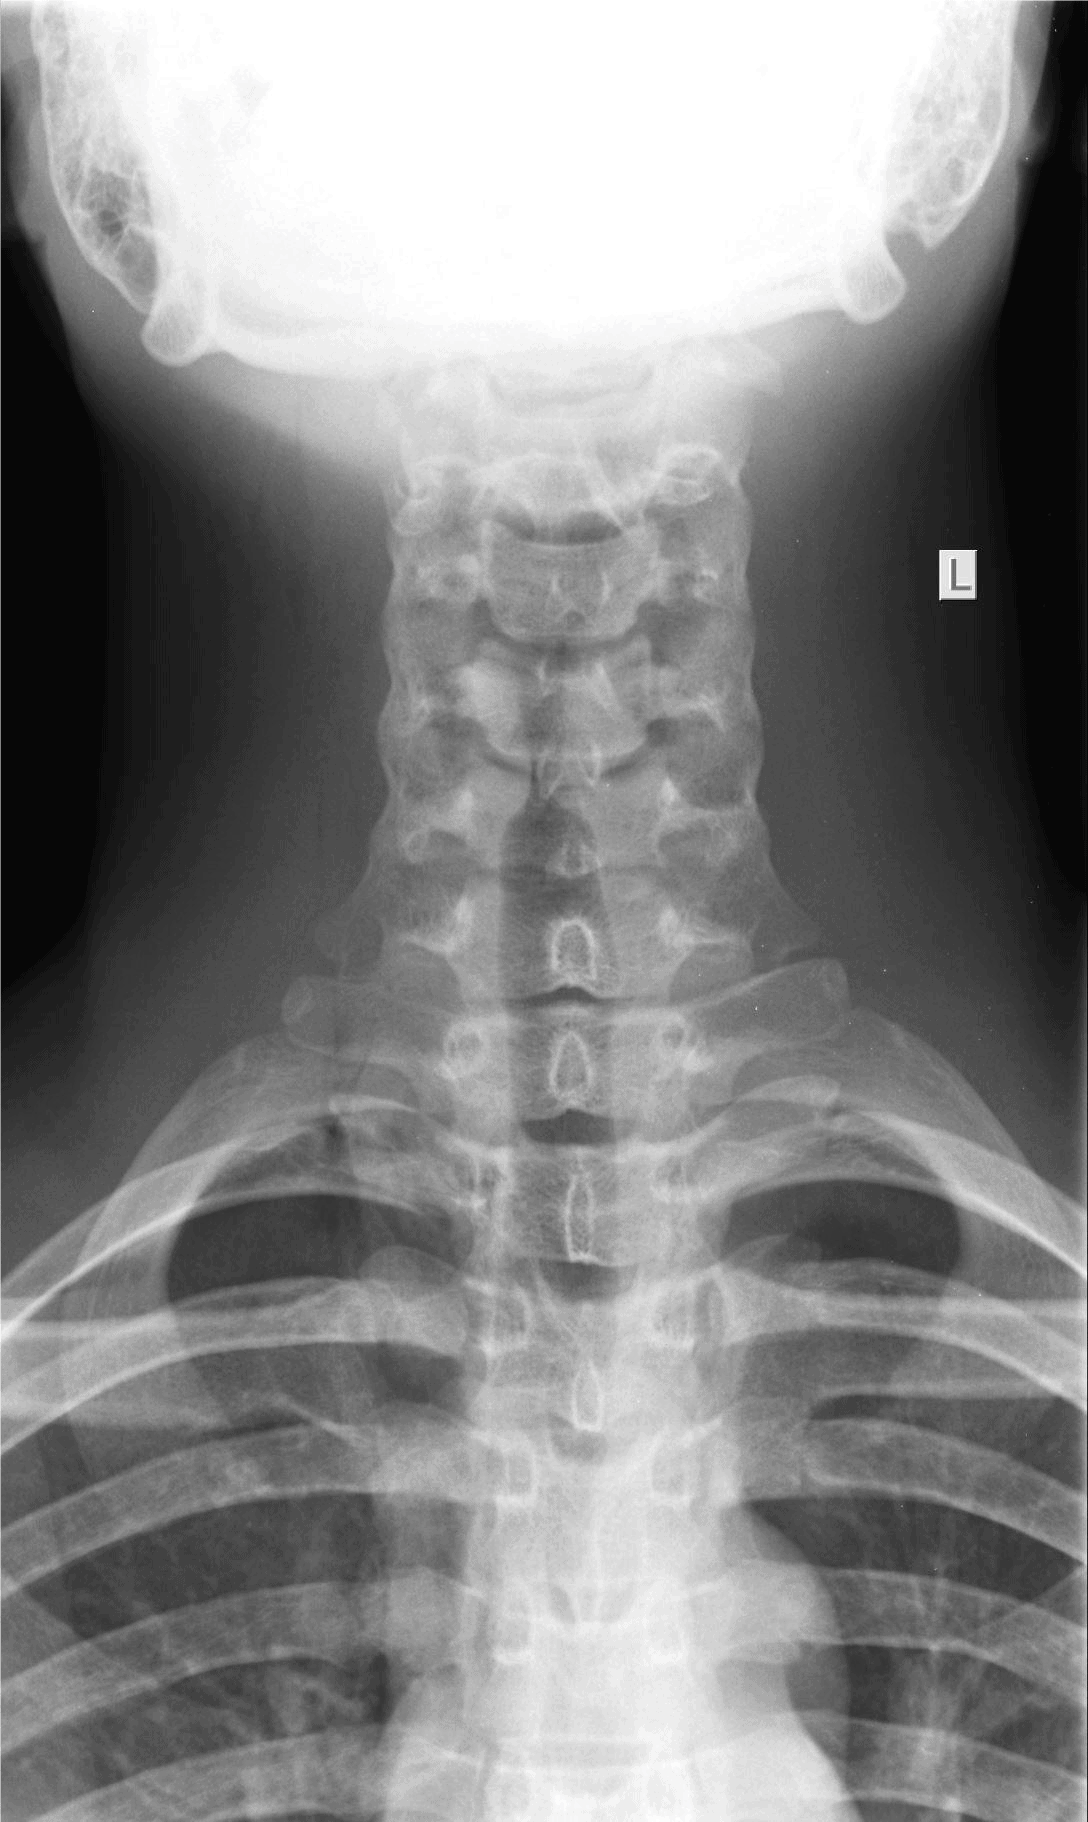

The patient is a 9-year-old girl who is brought in by her parents shortly after choking on a chicken nugget. They are concerned because even though she stopped gagging, she complains that it feels “like there’s something stuck in there.”

View the images, ordered to rule out a lodged foreign body, and consider what the diagnosis and next steps would be. Resolution of the case is described on the next page.